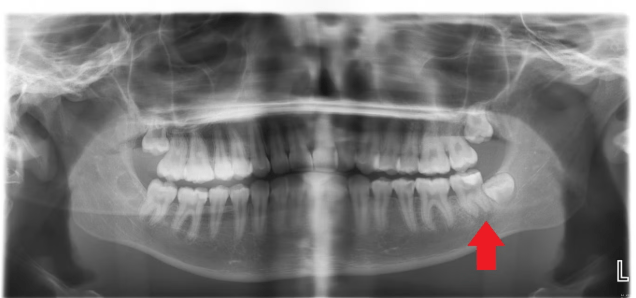

In the summer of 2021, then just 16, Katelyn visited the Skipton Road branch of Mydentist for pain related to a cracked tooth.

Instead of treating the underlying decay, the dentist simply cleaned the tooth and applied a sealant. Within weeks, the pain became unbearable.

When the pain and swelling intensified, Katelyn’s mother rushed her to Airedale General Hospital’s A&E. There, medics confirmed that the tooth should have been removed immediately and the abscess urgently drained.

Doctors performed emergency surgery under general anaesthesia. The tooth was extracted, and the abscess drained via an external incision, leaving Katelyn with a deep, open wound and a permanent scar roughly the size of a 50p coin.